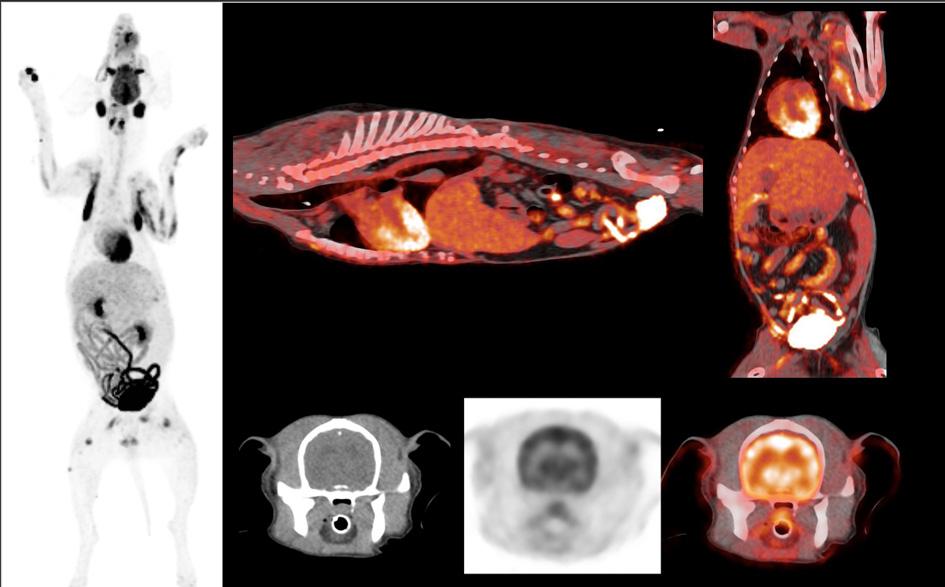

UW Veterinary Care (UWVC) is now offering PET-CT imaging, redefining how diseases are diagnosed and treated in animals.

PET-CT – which has been used for years in human medicine – represents a major leap in diagnostics at UWVC, especially in oncology. The non-invasive, whole-body scan can detect disease earlier than traditional imaging. The result? Informed decisions, personalized care, and more time with the pets we love.

The technology is “already proving invaluable for identifying cancer and monitoring its spread,” says Samantha Loeber (Department of Surgical Sciences), clinical assistant professor of diagnostic imaging. Faculty completed extensive training, with Loeber’s dogs, Shelby and Sawyer, helping ensure the process meets UWVC’s high standards.

PET-CT also supports sports medicine for canine and equine patients by identifying injuries and monitoring recovery, and helps distinguish between benign and malignant masses.

The technology bolsters a larger mission: advancing animal care worldwide and informing research that could help improve and save both animal and human lives.

“The insights we gain from studying diseases in animals often apply to human conditions,” Loeber says. “PET-CT offers a unique opportunity for translational research, where breakthroughs in veterinary care can directly benefit both animals and people.”